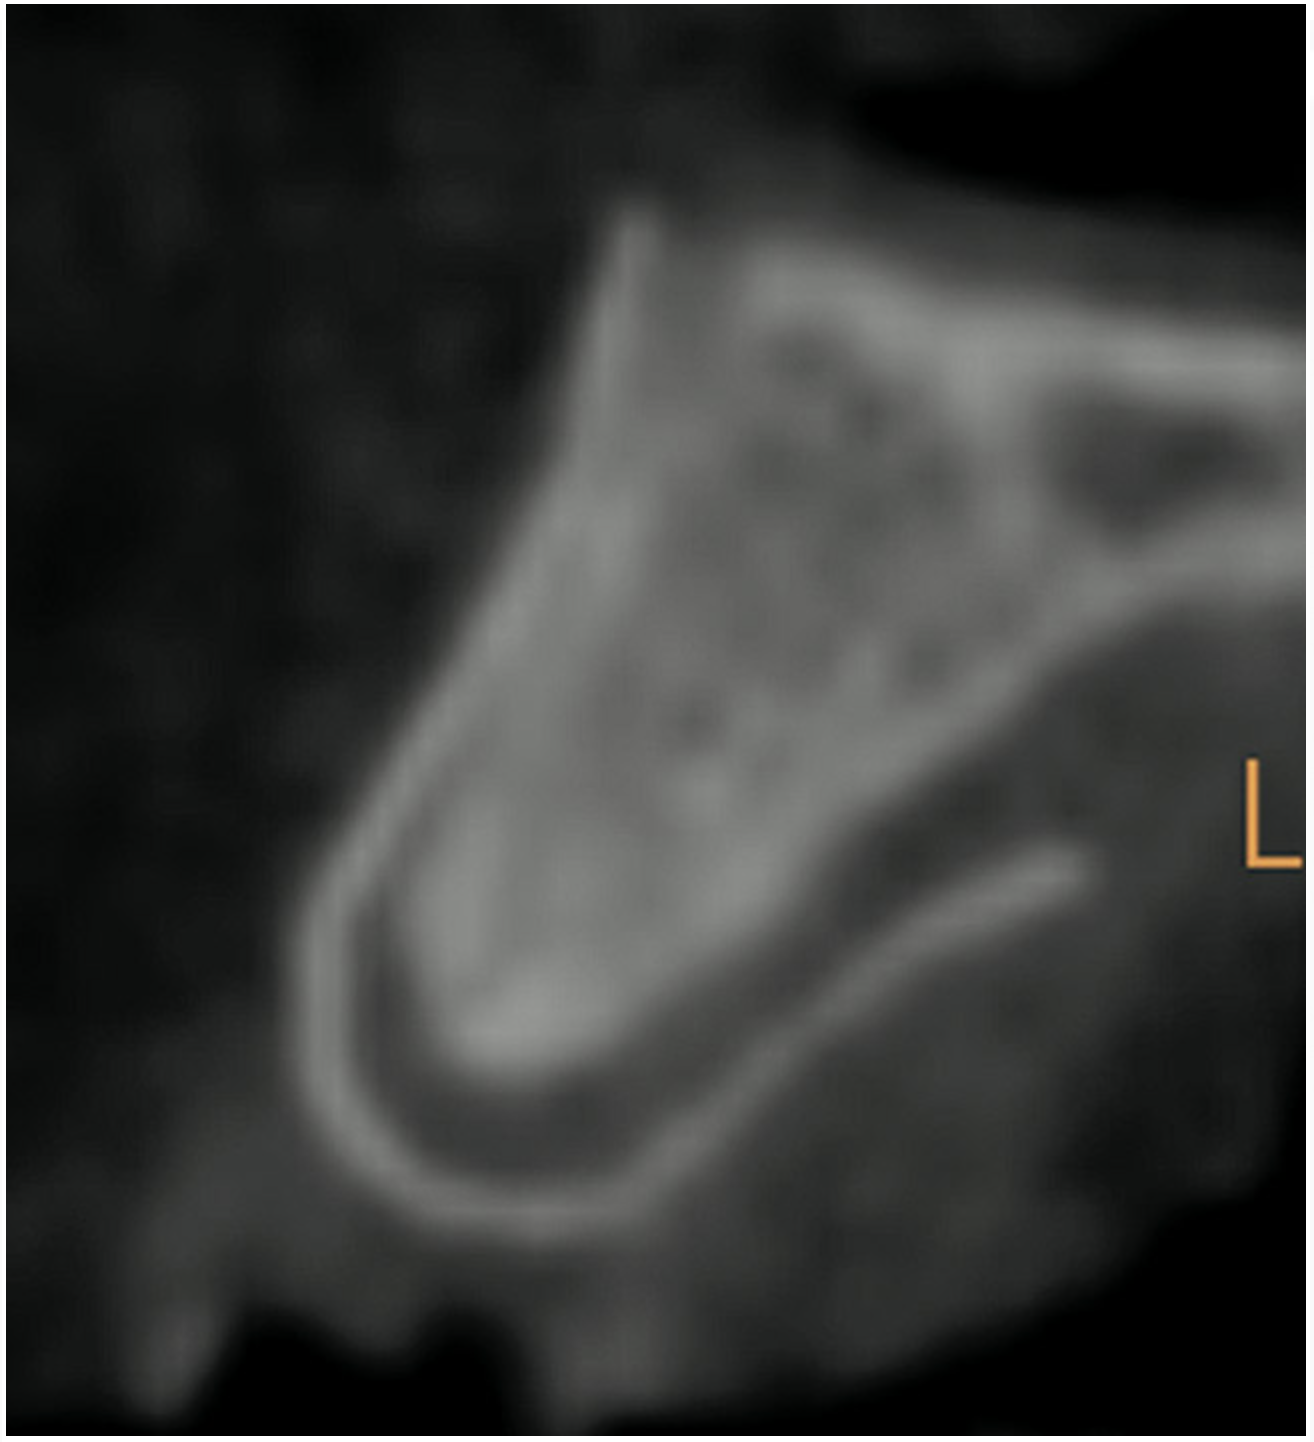

Figure 3  CBCT sagittal view. Note the extent of alveolar ridge deficiency.

Figure 3

Case 1

A 16-year-old female patient with a congenitally missing maxillary right lateral incisor was referred for an implant-supported crown. Clinical and CBCT evaluation revealed both a facial and palatal bony width deficiency (Figure 2 and Figure 3). The treatment plan included the use of titanium mesh and rhBMP-2/ACS (INFUSE® Bone Graft) along with mineralized allograft (MinerOss®, BioHorizons, www.BioHorizons.com) for bony augmentation (Figure 4 and Figure 5). After 7 months, the graft was found to be well incorporated and allowed for placement of a 3.8-mm x 10.5-mm diameter root form implant that was restored 3 months later (Figure 6, Figure 7, Figure 8, Figure 9 and Figure 10).